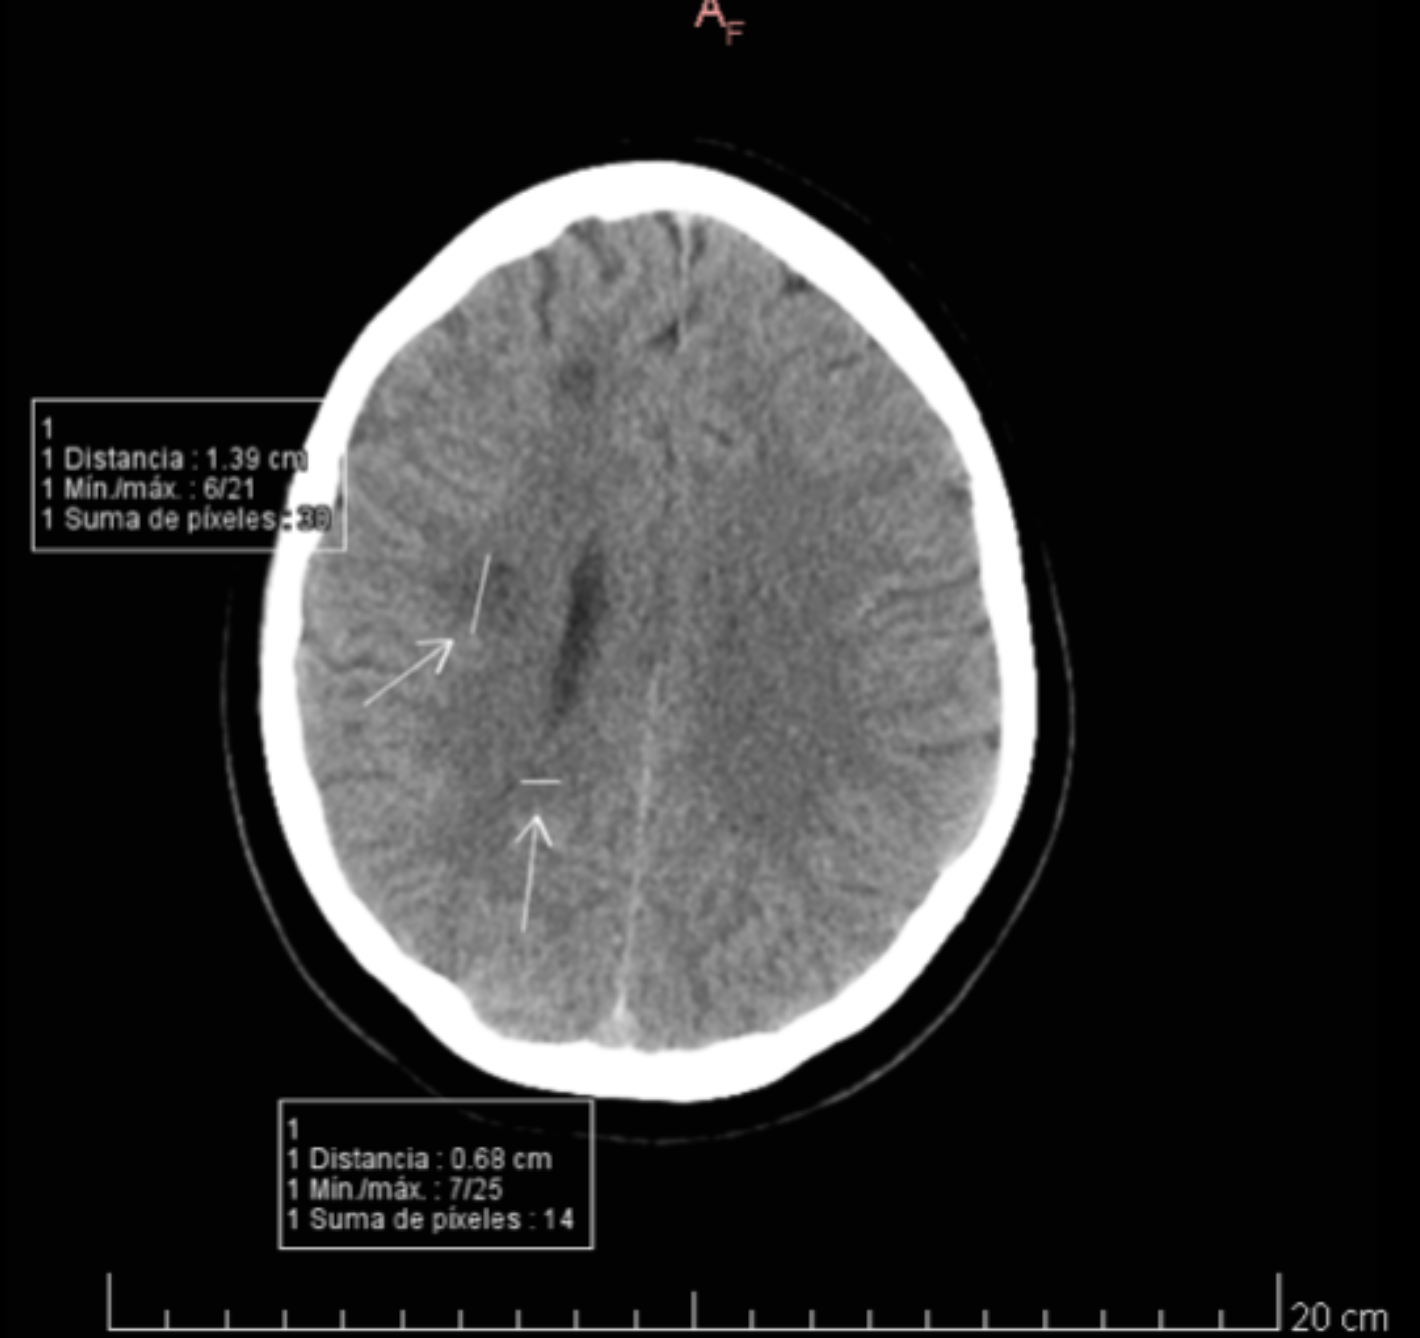

Se realiza un TC cerebral urgente en la que se observan dos lesiones hipodensas de márgenes mal definidos en el hemisferio cerebral derecho. Una de ellas, la de mayor tamaño, se localiza a nivel subcortical y la otra lesión se encuentra en el esplenio del cuerpo calloso.